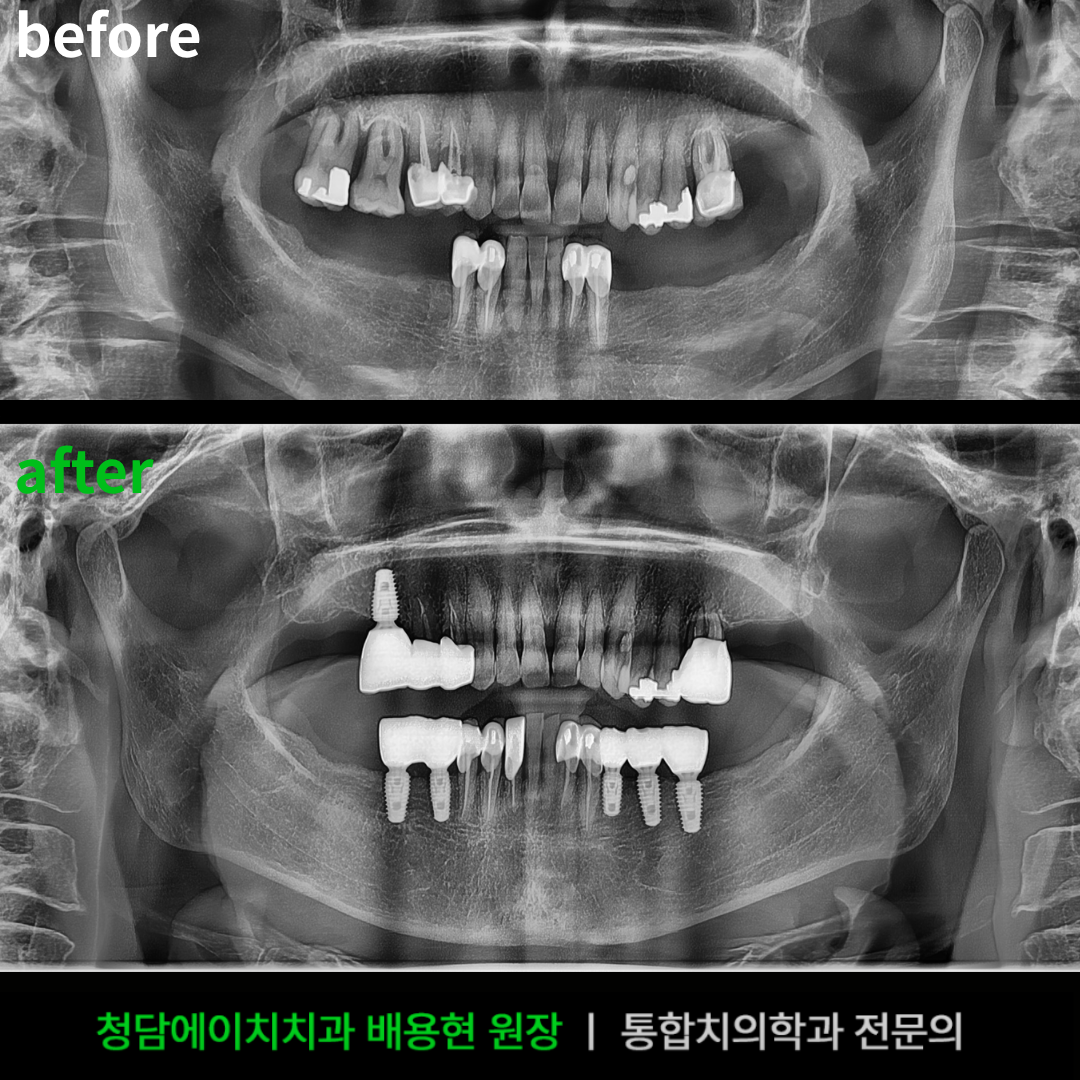

⭐ 청담에이치치과의원 포항양덕점: “저처럼 겁 많은 분들을 위한 치과 공포증 극복기”

제가 이 치과를 추천하는 가장 큰 이유는, “치과는 아프고 두렵다”는 환자 마음을 너무 잘 안다는 점이에요. 원장님 설명처럼 수면진정치료(진정 수면 마취)와 최적화된 마취 시스템으로 아픔을 줄이려고 노력한다고 합니다. 저도 임플란트 때문에 걱정 많았는데, 여기는 과정이 투명하고 빠르다는 게 진짜 장점이었어요.

이곳의 핵심은 원내에 기공사 선생님이 상주한다는 거예요. 보철물 제작 시간이 확 줄어들고, 제 치아에 맞게 바로바로 수정할 수 있어서 여러 번 왔다 갔다 할 필요가 없어요. 바쁜 저한테는 최고의 메리트였습니다!